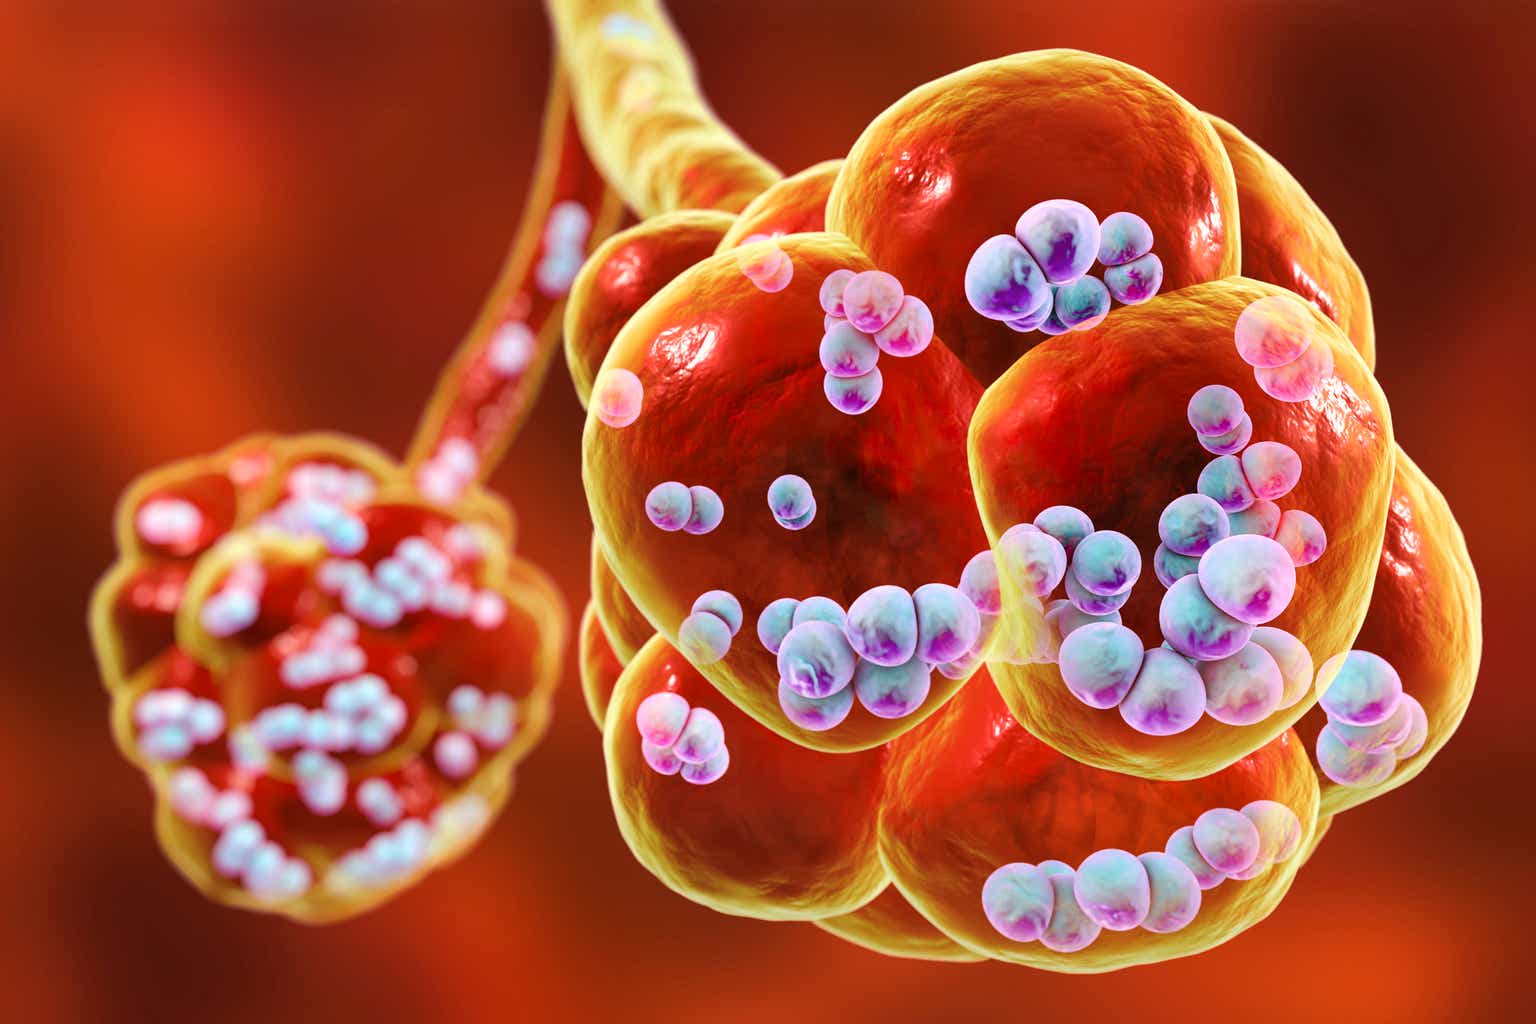

Фотографии бактерий, вызывающих бактериальные пневмонии у животных

Раздел: Другие животные